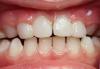

Екатерина Геранина Опубликовано 5 августа, 2013 Поделиться Опубликовано 5 августа, 2013 В продолжение истории со своим маленьким пациентом... Мостики консольные сняла-неудовлетворительная эстетика-большие по сравнению с его зубками,не смог привыкнуть... Сделала экспериментальную работу. Оттиски-модели-индивидуальные силиконовые колпачки-шинирующая лента-фотополимерный материал(ниже фото)к этим зубкам привыкает малыш быстрее,дикция лучше,эстетика лучше Ссылка на комментарий

ElenaD Опубликовано 5 ноября, 2013 Поделиться Опубликовано 5 ноября, 2013 Коронки припасовываем, детки привыкают хорошо к ним. Начали ставить только весной, пока все нормально. 1 Ссылка на комментарий